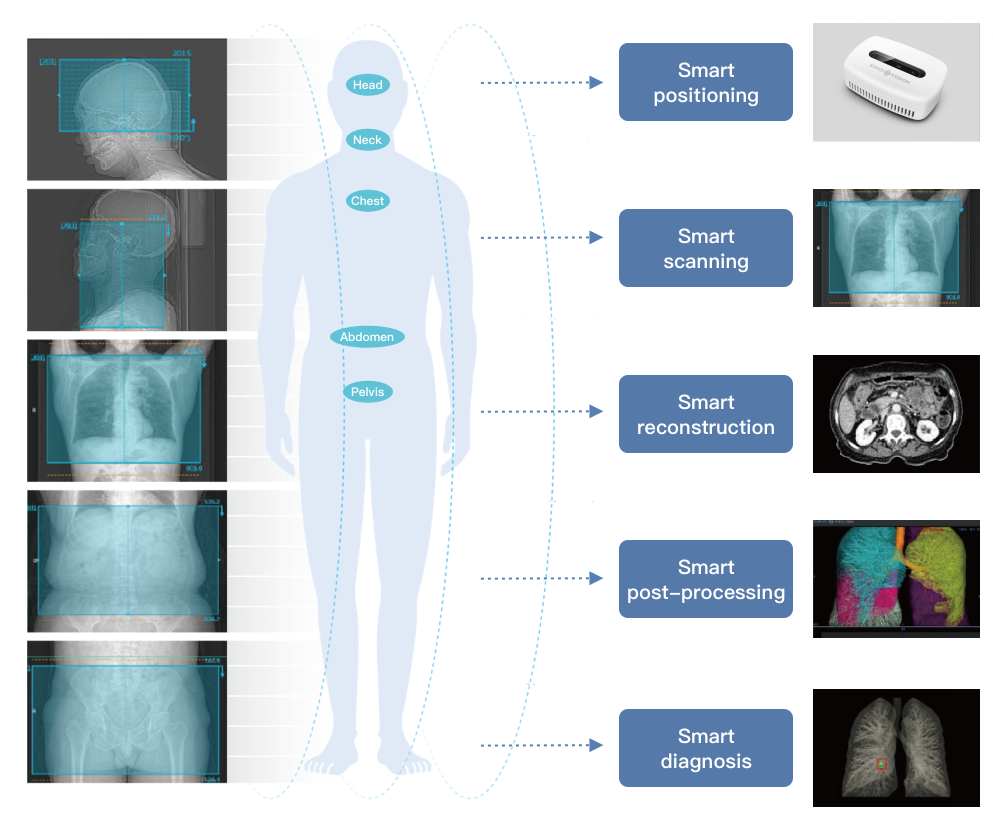

- Automatische Patientenpositionierung.

- Automatische Tischbewegung zur Scan-Mitte.

- Verbessert die Scan-Effizienz

- Fernbedienungsscan.

INTEGRIERTE ANWENDUNGEN:

• Interventionelle Abteilung: Biopsie, Ablation, Behandlung etc.

• Strahlentherapie: CT-Simulation.

• Onkologie: Tumordarstellung, -beurteilung, -überwachung, Therapiekontrolle etc.

• Orthopädie: 3D- und VR-Bildgebung, Frakturdarstellung.

• Medizinische Untersuchungsstelle: Niedrigdosis-Detektion, automatisierte Diagnose.

• Neurologie: Schlaganfallbeurteilung und vaskuläre Morphologieanalyse.

• Pneumologie: Lungenrundherdanalyse, Pneumonie und Lungenfunktionsprüfung.

• Radiologie: Ganzkörper-CT.